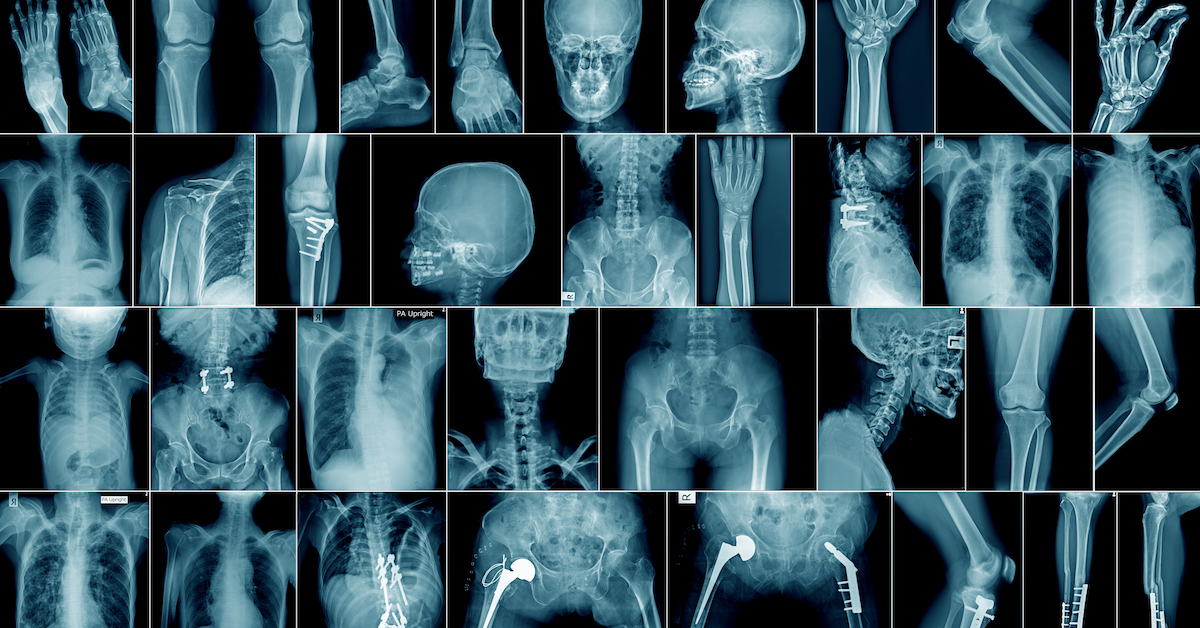

After asking about your medical history, general health, risk factors, and treatment expectations, your healthcare provider will perform a physical examination. This will likely involve the application of gentle pressure to the injured area to determine whether it causes pain, which may be an indication of some type of fracture. An X-ray or MRI may be required to confirm the diagnosis or to determine the exact type of fracture.